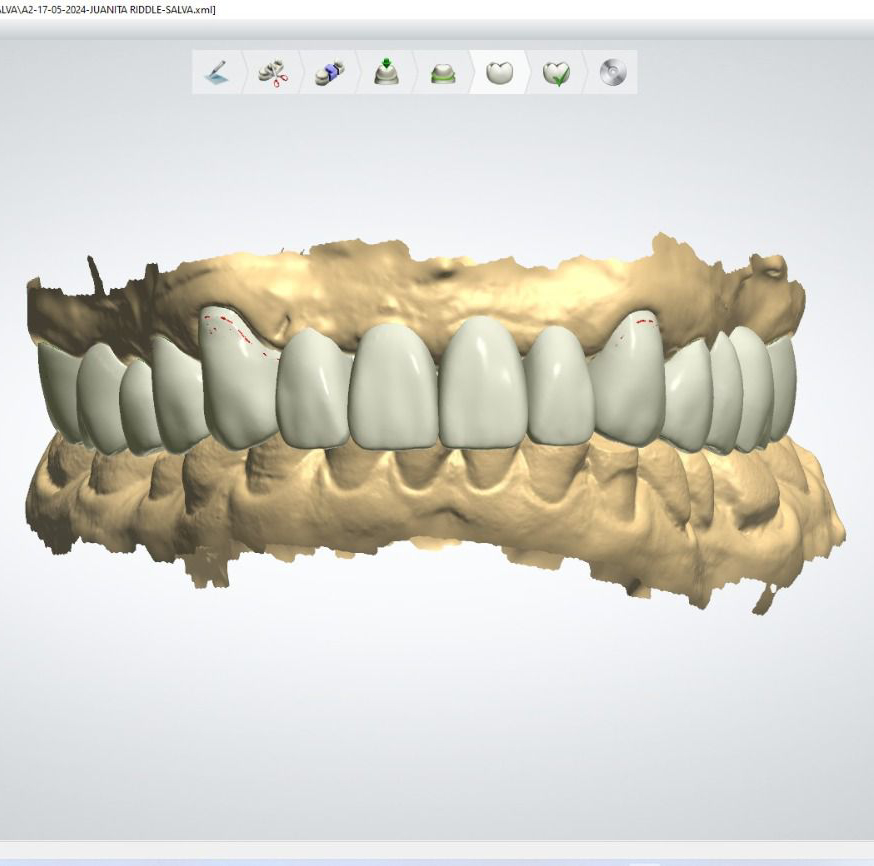

Casos de éxito

Estos son algunos de nuestros casos de éxito, mostrando el antes y después de nuestras intervenciones.

Rehabilitación superior e inferior con zirconia monolítico multicapa en color B1.